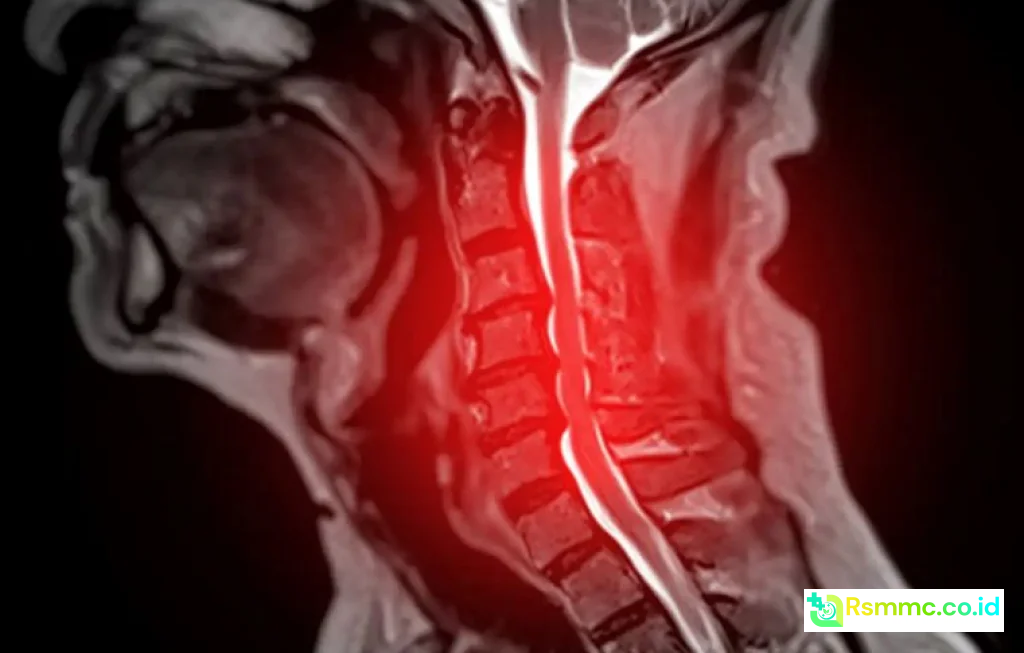

Di ruang radiologi, interpretasi MRI dan CT scan tulang belakang sangat menantang. Struktur anatomi rapat, dan perbedaan antara jaringan normal dan patologis sering tipis. AI Spinal Cord Disease Prediction menawarkan cara baru untuk membaca gambar dengan ketelitian tinggi.

AI Spinal Cord Disease Prediction pada Gambar MRI

MRI adalah modalitas utama untuk menilai sumsum tulang belakang karena mampu menampilkan jaringan lunak dengan jelas. Namun, membaca ratusan irisan gambar untuk satu pasien membutuhkan waktu dan konsentrasi tinggi.

Algoritma ini bekerja dengan memindai setiap piksel atau voxel, lalu mengidentifikasi pola tekstur, intensitas, dan bentuk yang konsisten dengan penyakit tertentu. Radiolog tetap memegang keputusan akhir, tetapi kini memiliki panduan visual yang lebih tajam.